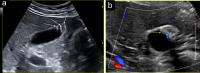

Gallbladder polyps are protuberances of the gallbladder wall projecting into the lumen. They are usually incidentally found during abdominal sonography or diagnosed on histopathology of a surgery specimen, with an estimated prevalence of up to 9.5% of patients. Gallbladder polyps are not mobile and do not demonstrate posterior acoustic shadowing; they may be sessile or pedunculated. Gallbladder polyps may be divided into pseudopolyps and true polyps. Pseudopolyps are benign and include cholesterolosis, cholesterinic polyps, inflammatory polyps, and localised adenomyomatosis. True gallbladder polyps can be benign or malignant. Benign polyps are most commonly adenomas, while malignant polyps are adenocarcinomas and metastases. There are also rare types of benign and malignant true gallbladder polyps, including mesenchymal tumours and lymphomas. Ultrasound is the first-choice imaging method for the diagnosis of gallbladder polyps, representing an indispensable tool for ensuring appropriate management. It enables limitation of secondary level investigations and avoidance of unnecessary cholecystectomies.